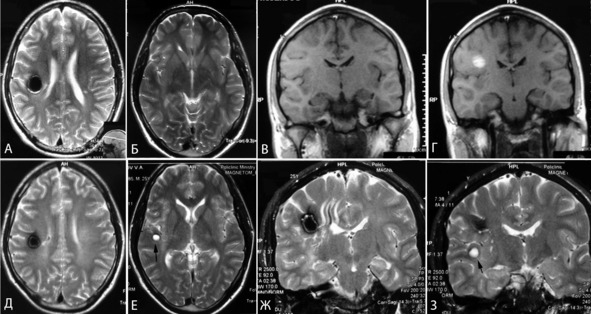

Для подтверждения образования каверномы de novo необходимо качественное исходное МРТ исследование, имеющее высокое разрешение. С учетом того, что изменения могли произойти даже с очень небольшой каверномой или каверномой IV типа по Zabramski, необходимо также исходно выполнить МРТ, взвешенное по неоднородности магнитного поля. У трех пациентов из нашей серии можно было предполагать появление каверномы de novo. В одном случае появление каверномы можно связать с курсом лучевой терапии после удаления медуллобластомы. Во втором – появление новой каверномы зафиксировано у больного с семейной формой каверном головного мозга на момент катамнестического осмотра. В третьем случае предпосылок к появлению новой каверномы не было (рисунок 22). МРТ-SWI у этих пациентов не выполнялась.

Рисунок 22. Появление каверномы de novo, МРТ в динамике. А, Б, В, Г – исходная МРТ. Д, Е, Ж, З – контрольная МРТ спустя 2 года. А, Б, Д, Е – МРТ в Т2 режиме, аксиальная проекция. В, Г – МРТ в Т1 режиме, фронтальная проекция. Ж, З – МРТ в Т2 режиме, фронтальная проекция. На рисунках Е и З стрелкой отмечен очаг подострого кровоизлияния (de novo образование каверномы?).